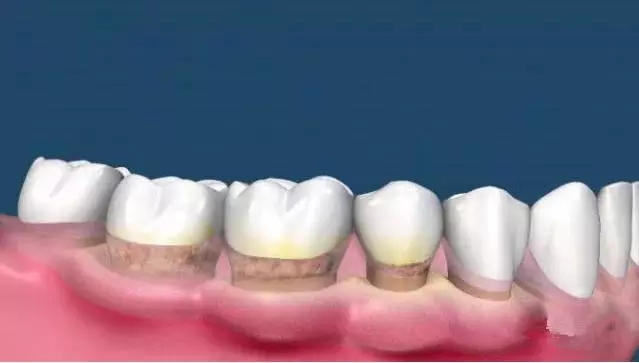

這時(shí)候很多人會(huì)發(fā)現(xiàn),齦上潔治和齦下刮治之后,很多人會(huì)發(fā)現(xiàn)牙根暴露在外面,而且牙縫明顯。

這是因?yàn)橄囱狼把例X的縫隙是因?yàn)槟切┛p隙里面填滿了牙結(jié)石,舌頭舔上去感覺不到,當(dāng)結(jié)石清除后,縫隙就會(huì)顯露出來。

而牙結(jié)石的堆積導(dǎo)致牙齦的退縮、牙根的暴露和牙槽骨的吸收,牙槽骨吸收以后是沒辦法恢復(fù)的,所以等到很嚴(yán)重才來看牙醫(yī)的時(shí)候,問題也許無法彌補(bǔ)了。

目前醫(yī)生盡最大的努力為患者保住了能夠保留的牙齒,保留不了的牙齒只能拔掉,然后再做種植修復(fù)。所以說,如果我們自己能夠有定期檢查、潔牙的意識(shí),也許結(jié)果就不會(huì)是這樣。

我們的牙齒就像一棵大樹,樹有樹根,埋在土壤里,所以很穩(wěn)定。

同樣地,牙齒的牙冠底下還有很長的牙根埋在周圍的齒槽組織里,所以牙齒才能穩(wěn)固在口腔內(nèi)行使咀嚼咬合的功能。